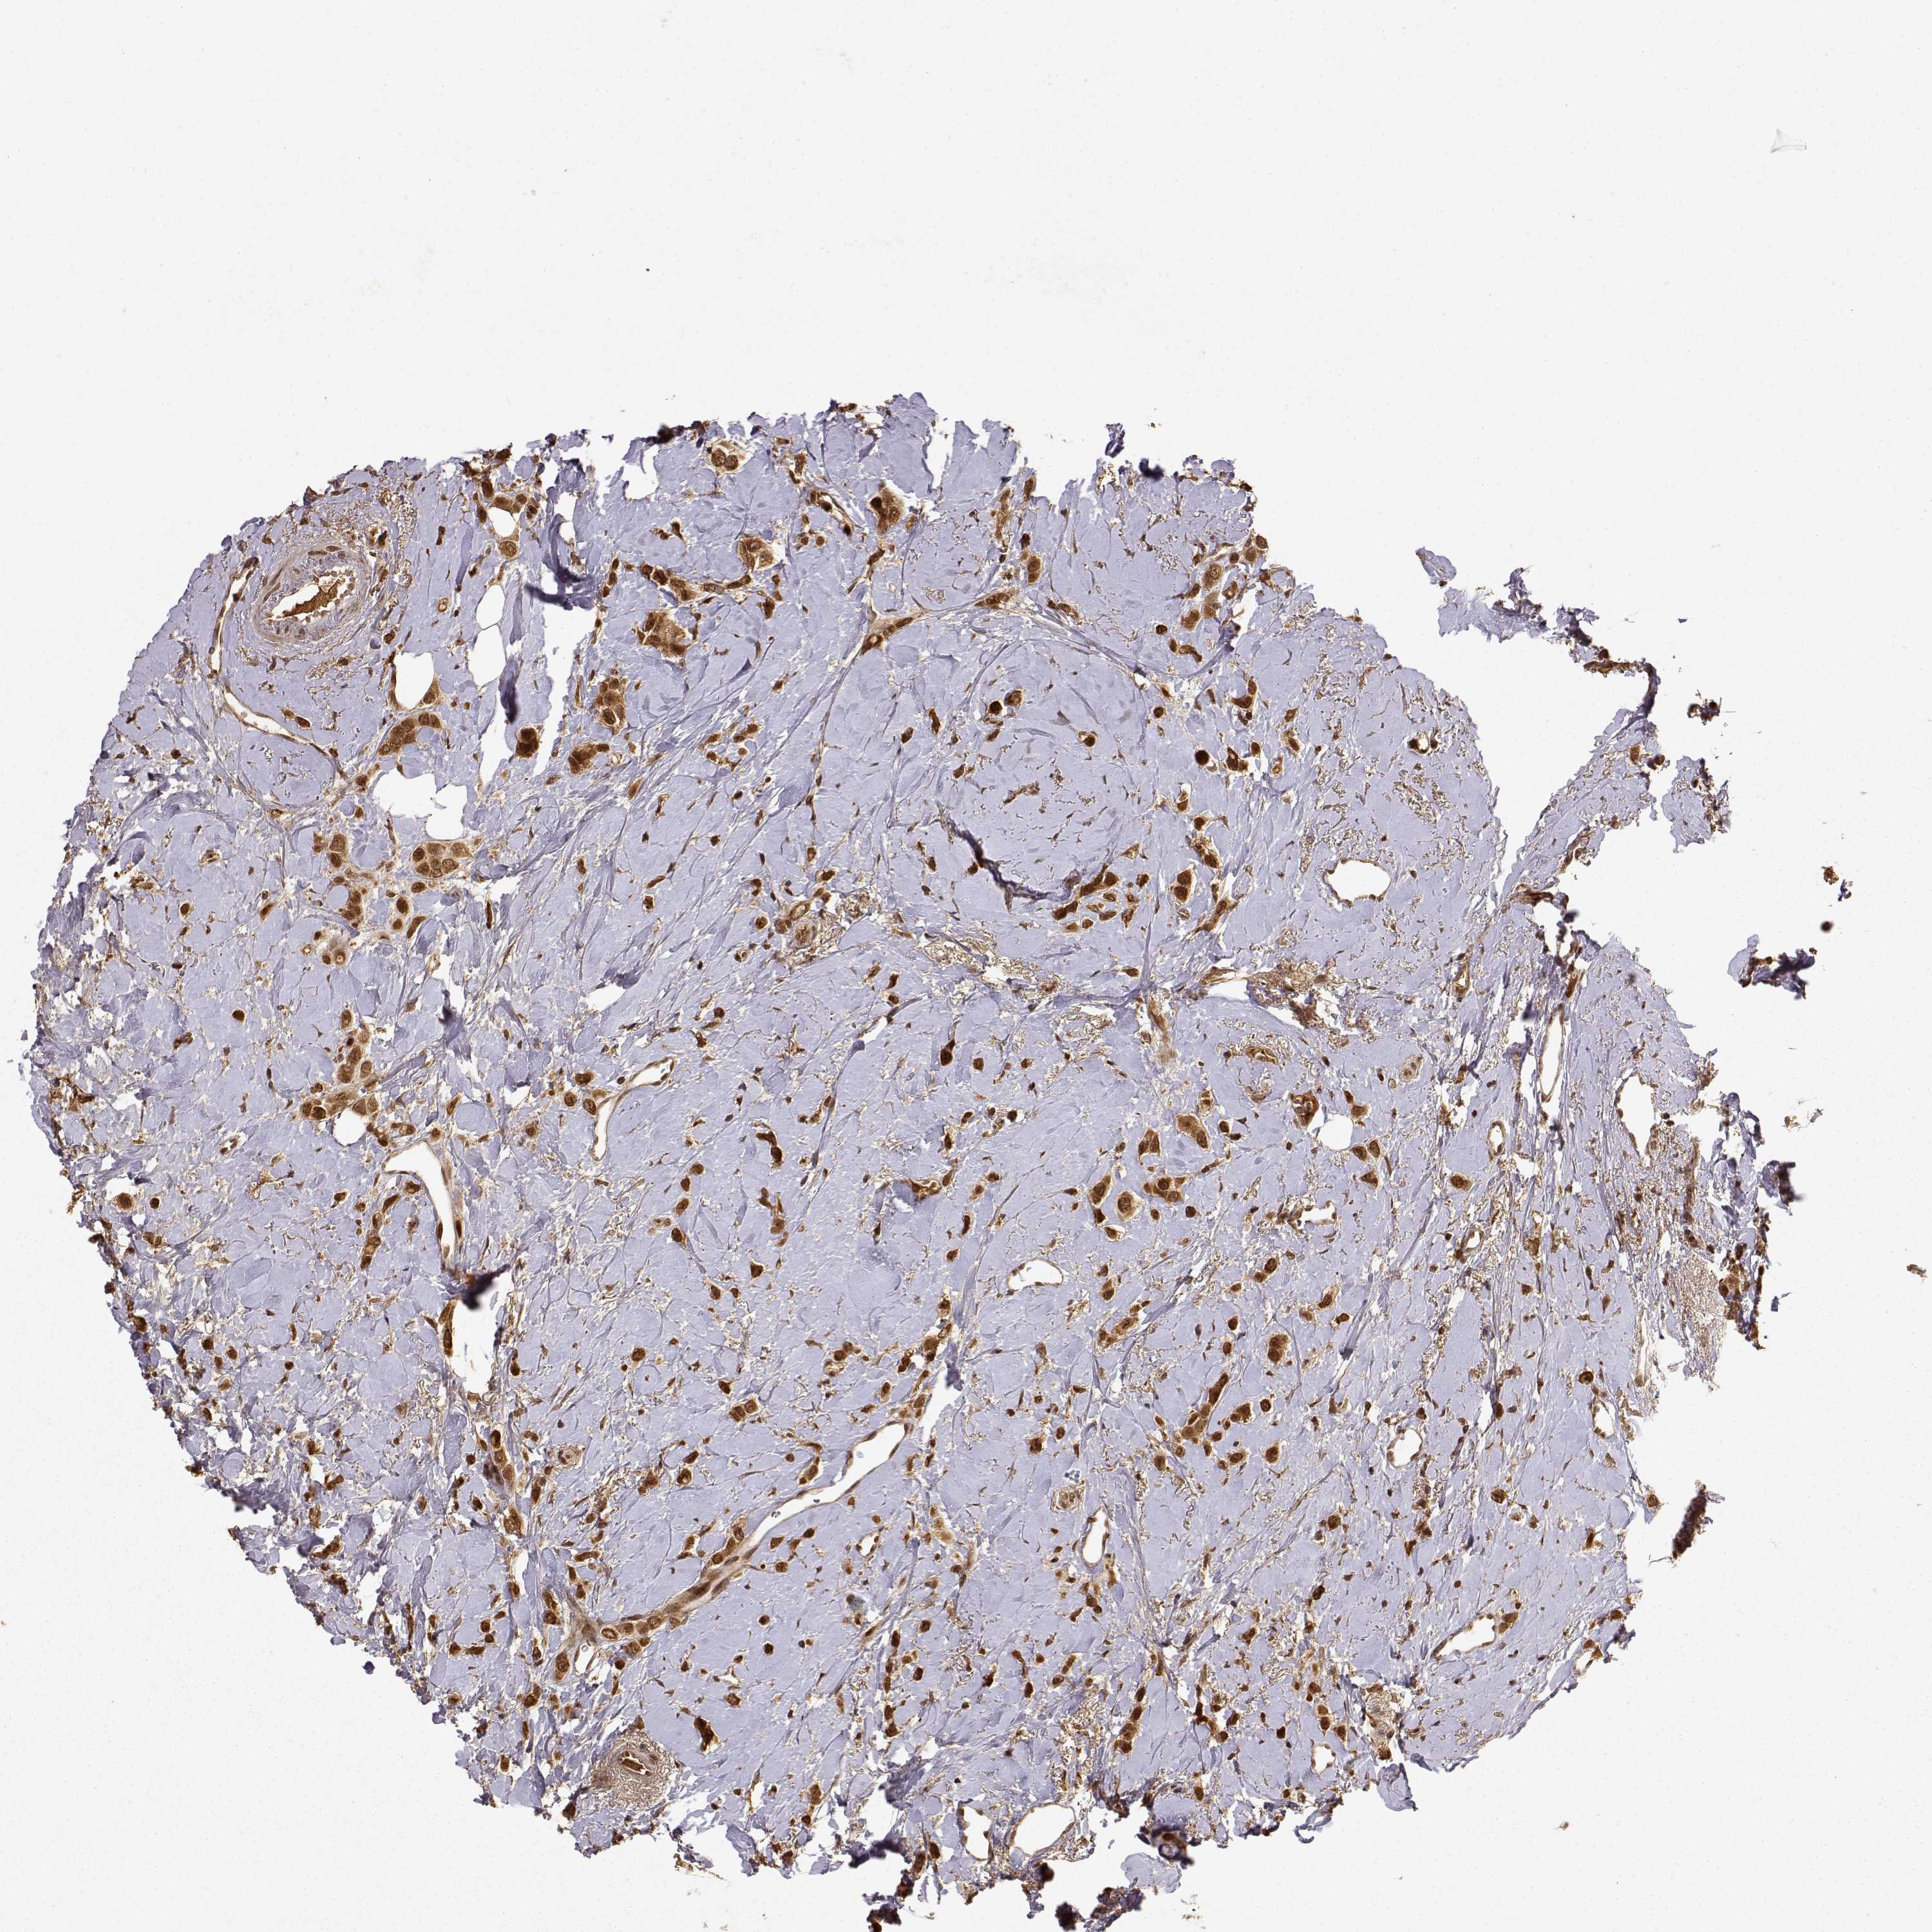

CANCER BREAST CANCER Show tissue menu

BRCA TCGA BRCA VALIDATION PROTEIN EXPRESSION

Breast cancer

Human cancer

MAEA is not prognostic in Breast Invasive Carcinoma (TCGA)